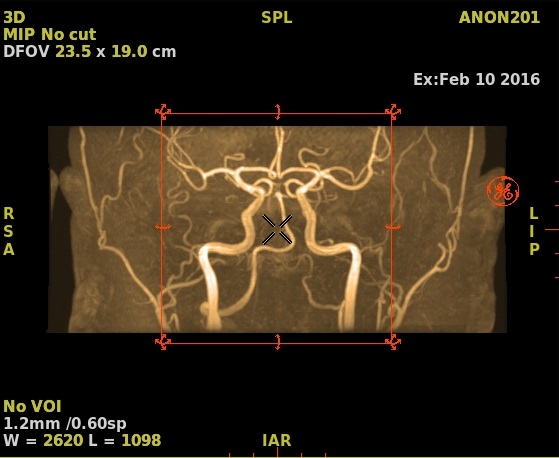

Figure 3. Example of Inverse gray on a MIP image

• Color to view the image in color. The effect varies based on the image type (parametric image, MIP, etc.).

Figure 4. Example of color on a MIP image